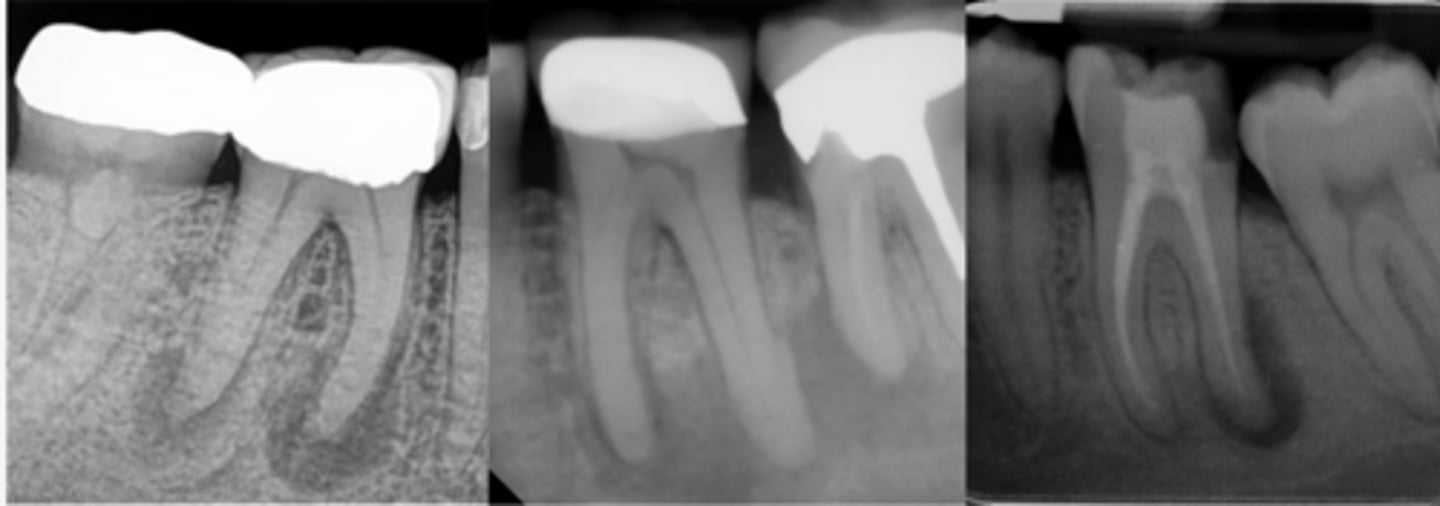

ID the problem:

- Ballooning out of root canal

internal resorption

How can you confirm if a root has internal resorption?

Take a few different angles